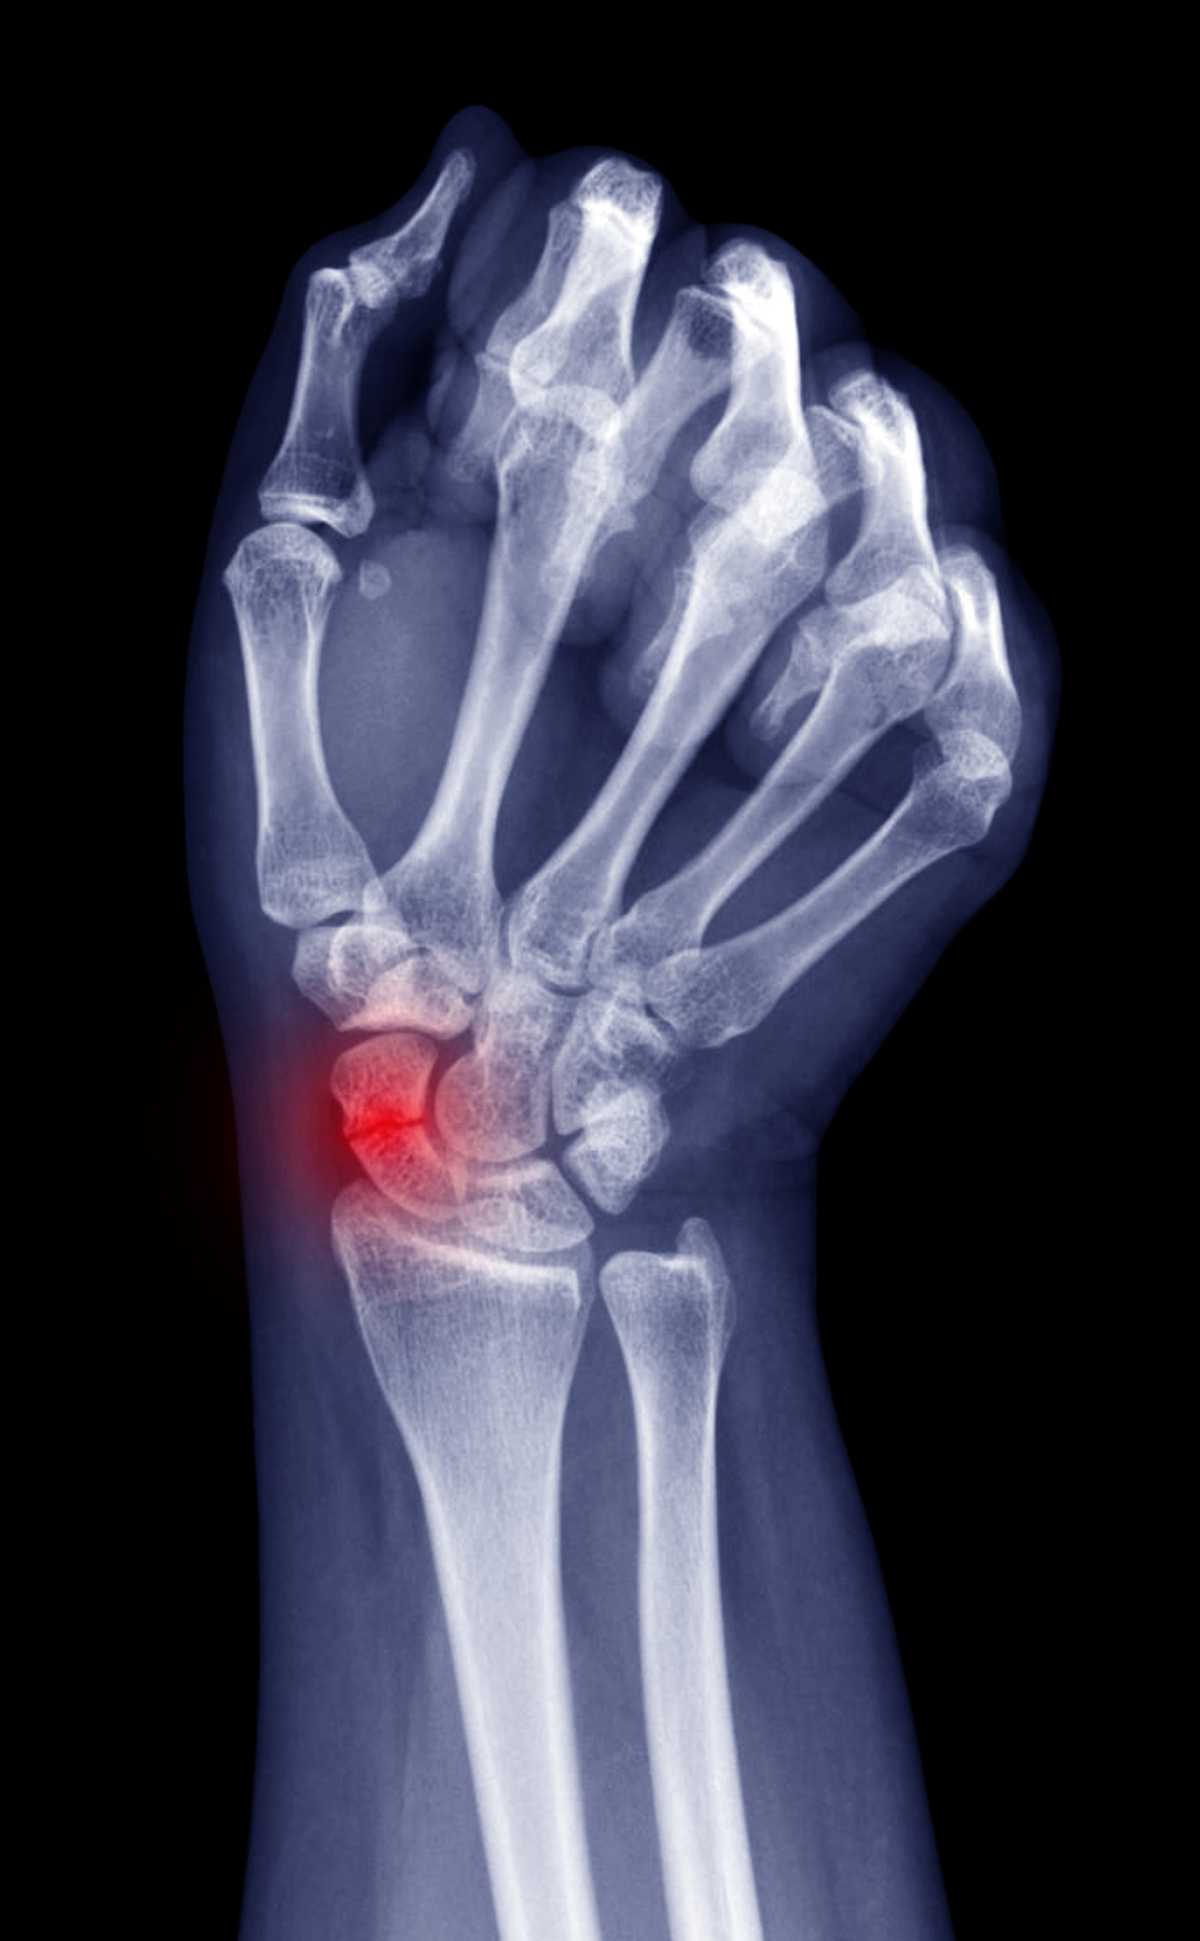

Radiographie d'une pseudarthrose du scaphoïde

Examen d'une pseudarthrose du scaphoïde